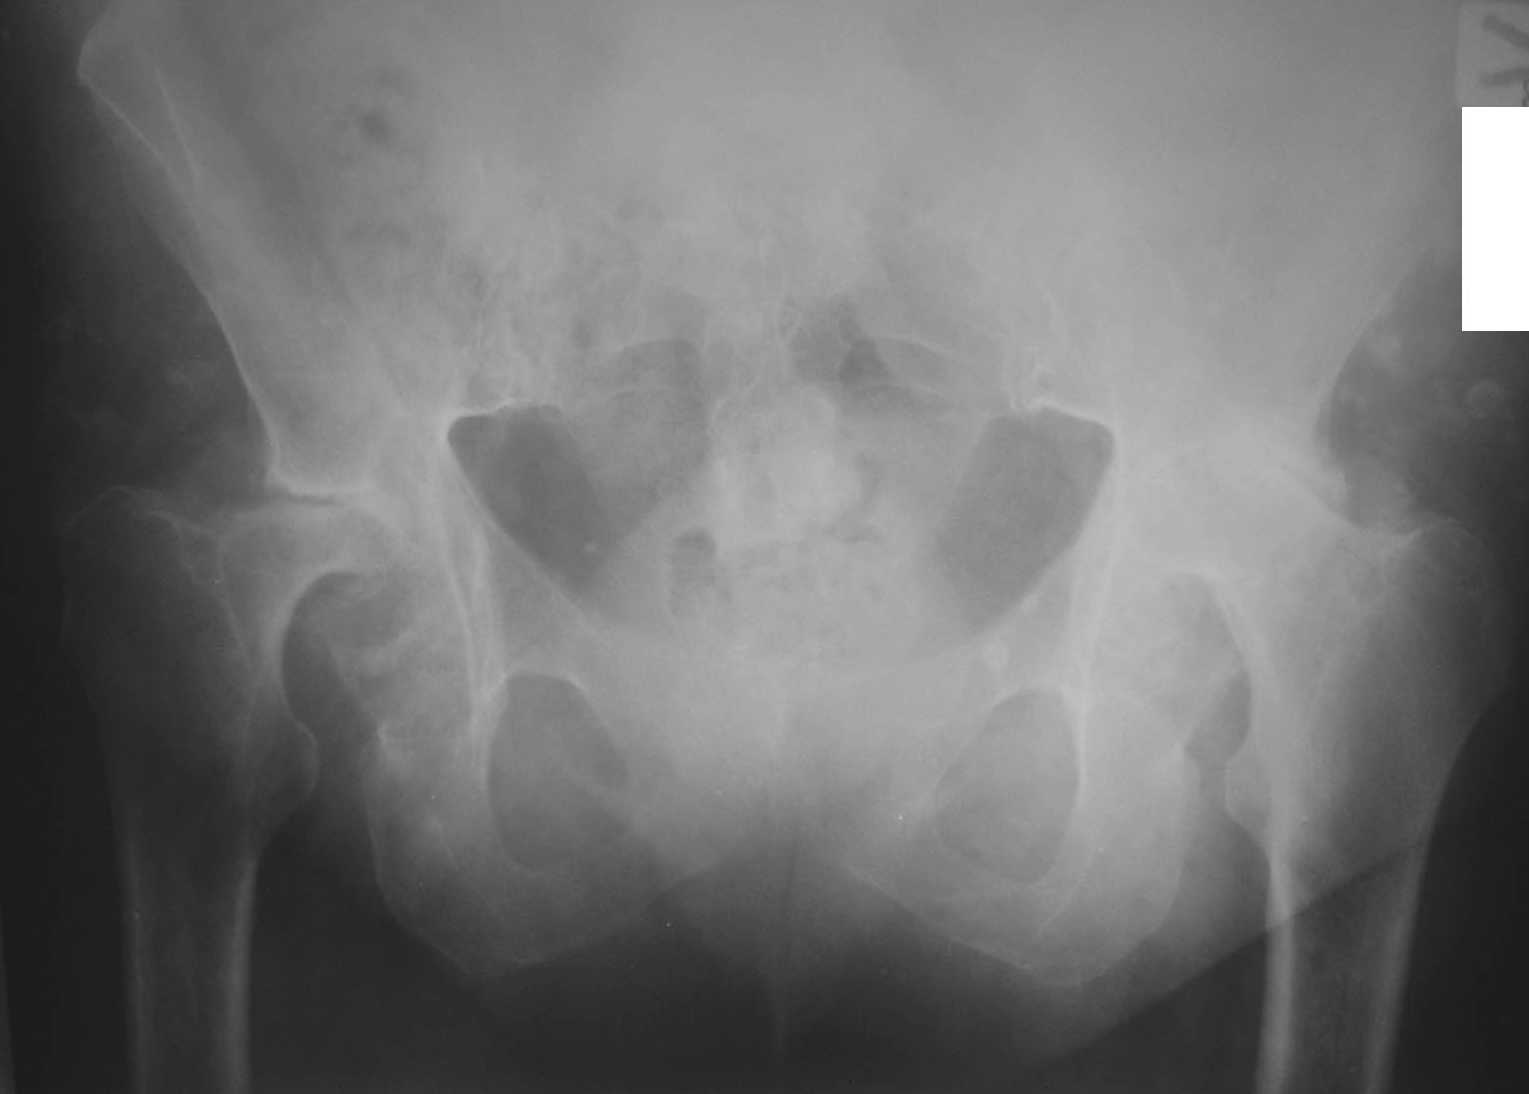

Пациентка С., женщина, 50 лет. Ревматоидный полиартрит. Двусторонний ревматоидный артрит тазобедренных суставов.инвалид 1-й гркппы. Принимает гормоны.

Вопрос: с учетом возраста и состояния костной ткани - цементную или бесцементную технологию эндопротезирования выбрать?

Заранее благодарю!Female, 50 y.o. DS: Rehumatoid polyarthritis, both-sides rehumatoid coxaarthritis.She has hormone therapy. We are going to perform arthroplasty.

Which kind do you prefer in this situation (cemented or cemented-less)?